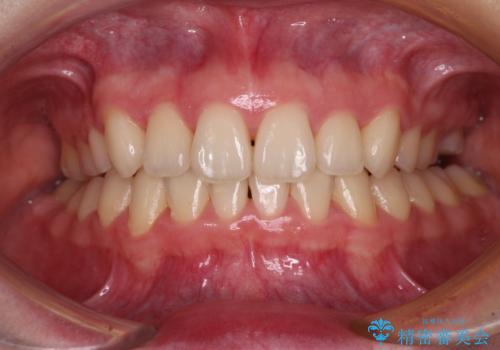

上顎のみの抜歯矯正 前歯のデコボコを改善する

奥歯の咬み合わせがなかなか定まらず、スペースが閉じるまでに時間がかかりましたが、最終的には正中を合わせることもできました。